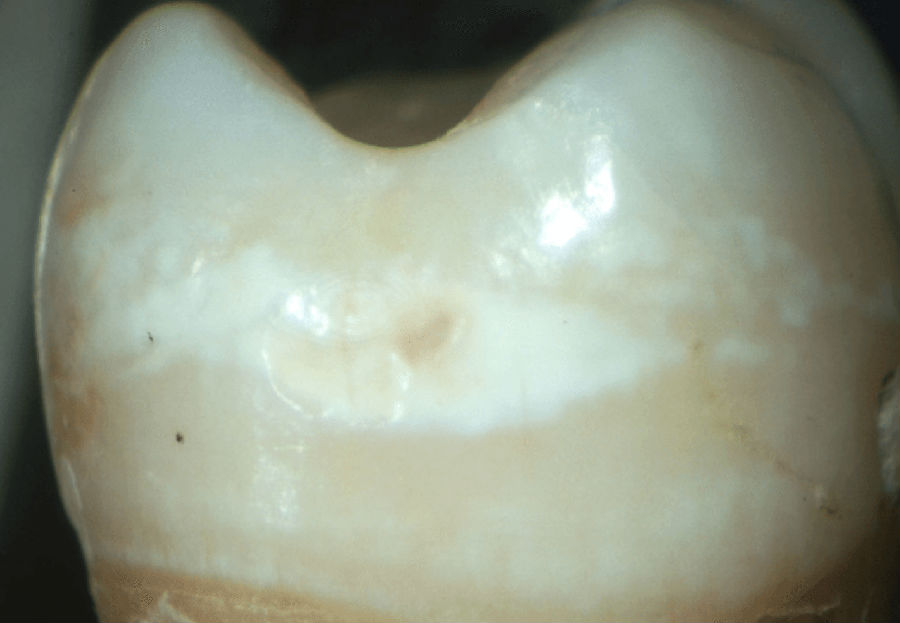

牙侵蚀症—由于酸侵蚀对牙齿造成的不可逆损伤。

图片来源:Geneva Dental Clinic, CC BY